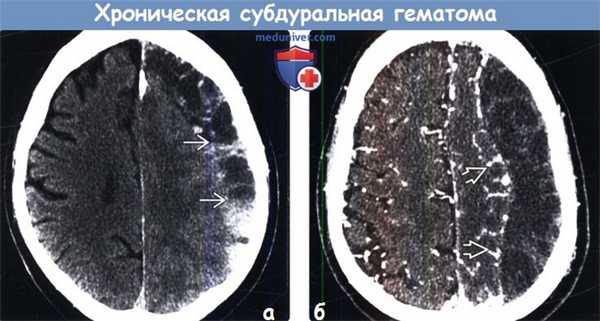

(а) Бесконтрастная КТ: у пожилого пациента с множественными падениями в анамнезе определяется разделенное на полости скопление «пенящейся» жидкости. Отмечаются многочисленные границы раздела кровь - жидкость.

(б) КТ-ангиография: у этого же пациента определяется скопление «пенящейся» жидкости в форме полумесяца. Обратите внимание на смещение кнутри головного мозга, а также компрессию борозд и смещение корковых вен.